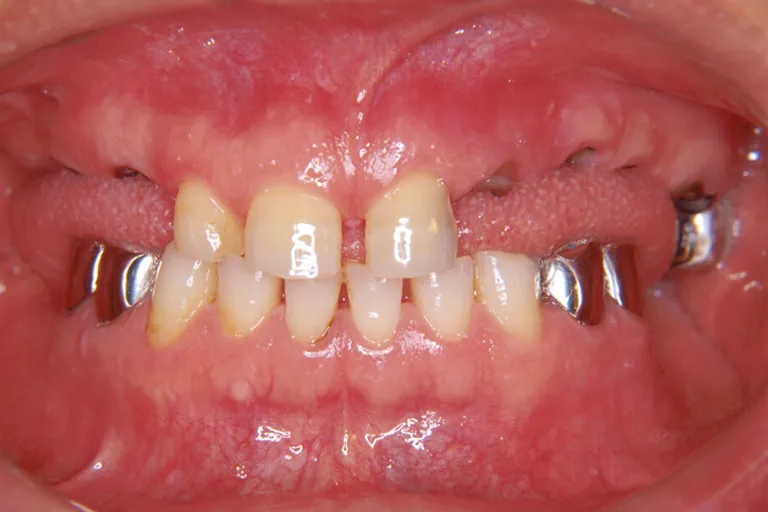

■術前の状態■多くの治療跡があり上顎は大半の歯が失われています総合的に見直して治療する必要があります

■術前の状態■

多くの

治療跡があり

状態が悪い

■術後の状態■インプラント・メタルボンド・アタッチメント義歯を含む包括的治療の例です

■術後の状態■

様々な治療法を

用いた

包括的治療の一例

■術後の状態■しっかりと噛める強度と快適な装着感で外からは自然な見た目です

しっかり噛める

口腔環境にします